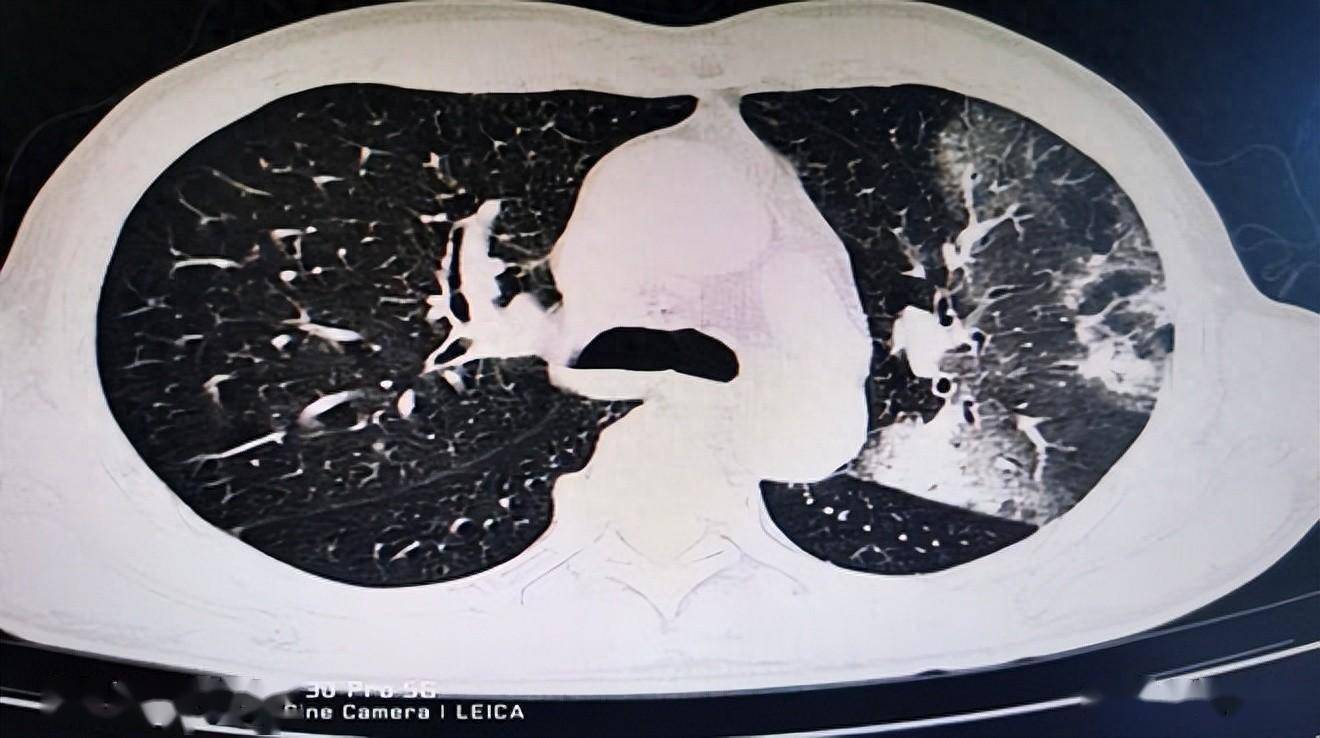

患者胸部ct示右下肺肺炎鹦鹉热是一种人畜共患的传染病,主要是由革兰

图片尺寸1080x675